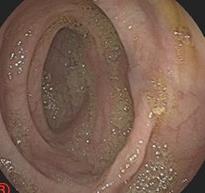

摘要:目的 探讨利那洛肽联合西甲硅油与复方聚乙二醇电解质散(PEG)对便秘患者肠道清洁效果的有效性和安全性。方法 采用前瞻性随机对照试验,通过单盲法,纳入2023年4月-2024年8月于该院消化内镜中心行结肠镜检查的便秘患者383例,随机分为常规组(128例)、实验A组(128例)和实验B组(127例)。常规组采用3 L PEG(Ⅰ)溶液,实验A组采用290 μg利那洛肽 + 2 L PEG溶液,实验B组采用290 μg利那洛肽 + 30 mL西甲硅油+2 L PEG溶液。比较3组患者的肠道准备效果[Boston肠道准备量表(BBPS)评分和去泡效果]、病变检出率、首次排便间隔时间、排便次数、盲肠插管成功率、进镜时间、退镜时间、不良反应发生率和重复检查意愿等。结果 3组患者BBPS评分比较,差异无统计学意义(P > 0.05);实验B组的去泡效果评分明显低于常规组和实验A组,差异均有统计学意义(P < 0.05);实验B组的病变总检出率和息肉检出率明显高于常规组和实验A组,差异均有统计学意义(P < 0.05);常规组的首次排便间隔时间明显长于实验A组和实验B组,差异均有统计学意义(P < 0.05);3组患者排便次数比较,差异无统计学意义(P > 0.05);3组患者盲肠插管成功率均为100.0%,进镜时间相当,差异均无统计学意义(P > 0.05);实验B组的退镜时间明显短于常规组和实验A组,差异均有统计学意义(P < 0.05);常规组腹胀腹痛发生率和不良反应总发生率明显高于实验A组和实验B组,差异均有统计学意义(P < 0.05);常规组重复检查意愿率明显低于实验A组和实验B组,差异均有统计学意义(P < 0.05)。结论 290 μg利那洛肽联合30 mL西甲硅油与2 L PEG溶液方案在便秘患者肠道准备上具有优势,较3 L PEG溶液和290 μg利那洛肽+2 L PEG溶液方案,可获得更好的肠道清洁效果,且安全性和患者重复检查意愿率高,可作为便秘患者肠道准备的推荐方案。

摘要:目的 探讨无痛结肠镜前顿服与不同剂量间隔12 h分次口服聚乙二醇电解质散剂(PEG)对肠道清洁效果的影响,以期优化肠道准备方案,提高患者的耐受性。方法 选择2024年6月-2024年9月在该院消化内科内镜中心接受无痛结肠镜检查,并使用PEG作为肠道清洁剂的患者232例作为研究对象。将参与者分为3组:对照组(3.00 L PEG顿服组)、试验A组(0.75 L+2.25 L PEG组)和试验B组(1.50 L+1.50 L PEG组),所有患者均在服用完毕后4 ~ 6 h内进行无痛结肠镜检查。其中,试验A组和试验B组两次服用PEG的间隔时间均为12 h。通过波士顿肠道准备评分(BBPS)评估肠道清洁度,并记录结肠息肉检出率、患者不良反应、睡眠时间及耐受性。结果 3组患者BBPS评分和结肠息肉检出率比较,差异均无统计学意义(P > 0.05)。试验B组服用PEG后的不良反应最轻,其次是试验A组,对照组的不良反应最明显(P < 0.05)。不同时间口服PEG对3组患者的睡眠时间无明显影响(P > 0.05)。试验B组对PEG的耐受性良好,愿意接受此方案进行肠道准备,试验A组次之,对照组耐受性最差,3组之间比较,差异有统计学意义(P < 0.05)。结论 顿服与分次服用PEG对肠道清洁效果及结肠息肉检出率无明显影响,但间隔12 h分次PEG方案,患者不良反应轻、耐受性好,尤其是间隔12 h分2次服用1.50 L PEG方案最佳。